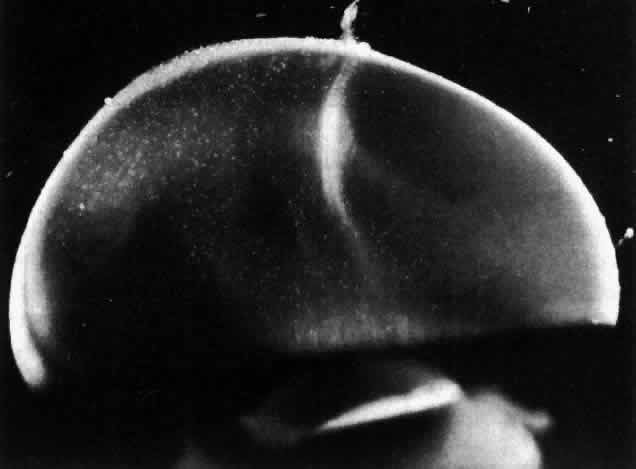

Fig. 10. Human vitreous morphology in old age. The central vitreous has thickened, tortuous fibers. The peripheral vitreous has pockets that do not scatter light. These areas contain liquid vitreous and correspond to lacunae as seen clinically on biomicroscopy. (Sebag J, Balazs EA: Human vitreous fibres and vitreoretinal disease. Trans Ophthalmol Soc UK 104:123, 1984)

During childhood only the vitreous cortex scatters incident light and thus appears dense (Fig. 9). There are no visible fibers within the corpus vitreous until middle age (see Figs. 4 THROUGH 6). During old age these fibers become thickened and tortuous, associated with many pockets of liquid vitreous and a collapsed (syneretic) appearance (Fig. 10). These changes are the result of age-related biochemical alterations in the composition and organization of the molecular components that simultaneously result in vitreous liquefaction and fiber formation. Pockets of liquid vitreous have classically been called “lacunae.” In addition to having a low density of collagen during youth, the central vitreous is the first region to undergo liquefaction during middle age.16 A report by Kishi and Shimizu18 described the presence of a “posterior vitreous pocket” that the authors interpreted to represent an anatomic entity. However, over 95% of the eyes examined in that study were from persons aged 65 years or older. Thus, these findings represent the result of age-related vitreous liquefaction in the central precortical posterior vitreous.93 Such changes could also explain the preferential pooling of aqueous dyes such as India ink17 placed onto the anterior vitreous and allowed to collect anterior to the macula in what appears as a “bursa.”17,94,95 The use of fluorescein by Kishi and Shimizu18 represents but another way of demonstrating the phenomenon of vitreous liquefaction in this region.